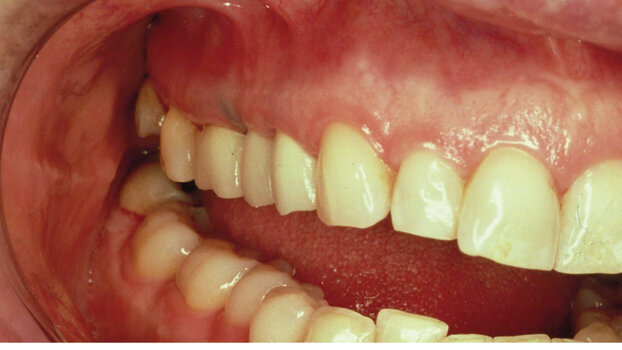

A second case demonstrates the use of the same technique in the posterior segment of a patient’s maxilla. An extreme buccal-incisal defect (Figs. 9, 10) where an extraction was done is shown in a maxillary posterior area (Fig. 11). The soft-tissue ridge augmentation technique was done. A temporary provisional bridge shows the restored ridge enhancing the cleanliness and cosmetic appearance. The final prosthesis displays a prosthetic appliance that has been in her oral cavity for 20 years. This shows the longevity as well as the esthetic enhancement of the technique and its ability to enhance the prosthesis. The finished prosthesis, which is easily maintained by the patient, shows that the unesthetic, unphysiologic defects were successfully corrected (Figs. 12, 13).